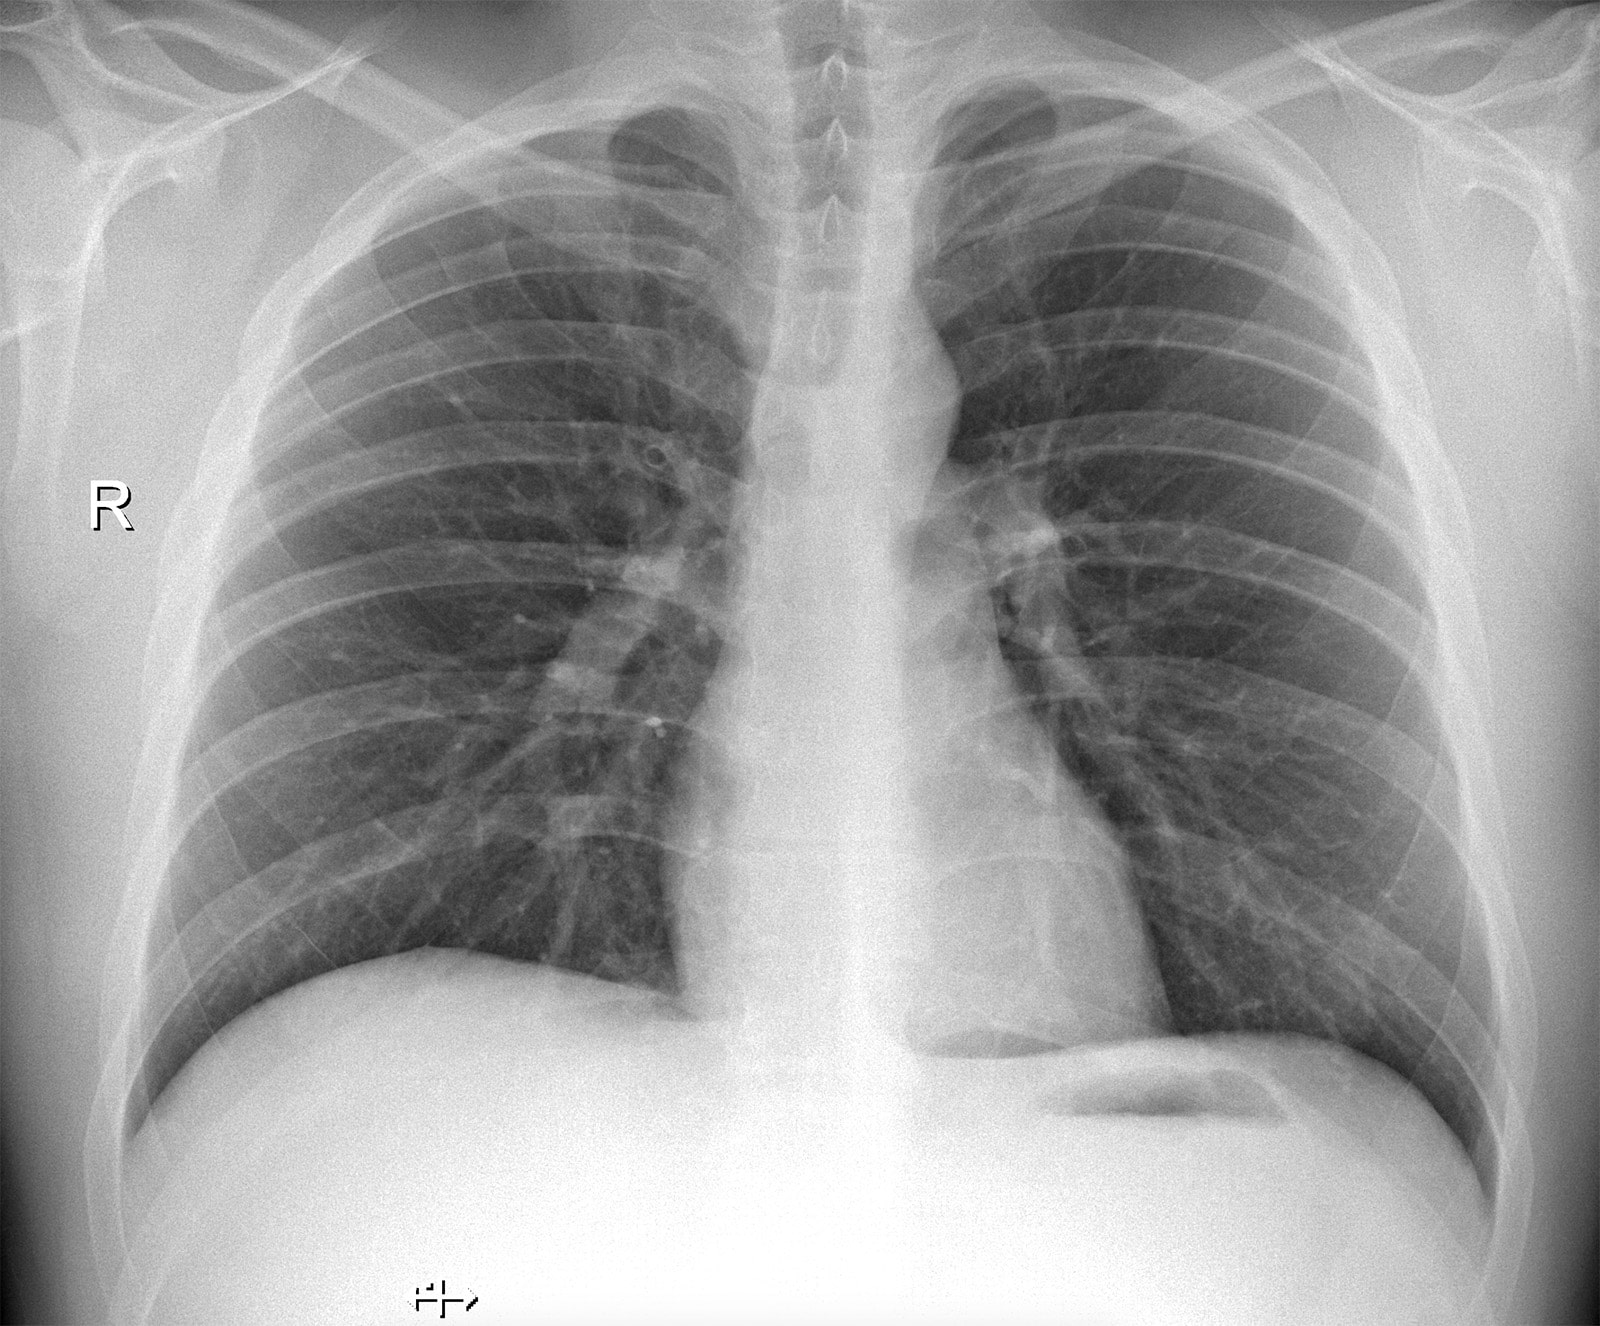

Рентгенография (Рентген) - метод лучевой диагностики, позволяющий получить изображения любой части тела. Пациент становится у стойки аппарата или располагается на специальном столе. Длительность исследования - несколько секунд. Оборудование низкодозное (0,02-0,04 мЗв) и безопасно для здоровья пациентов, в том числе для детей. Флюорография проводится методом цифровой рентгенографии с высоким разрешением, при этом лучевая нагрузка ниже в десять раз, чем при обычной флюорографии.

Рентген от производителя Siemens (Германия) позволяет получать изображения любой части тела. Включает в себя инновационные технологии, реализуемые в экспертных рентгеновских установках, что обеспечивает высокое качество изображения.

Данный рентгеновский аппарат является низкодозным, что особенно важно при обследовании детей.